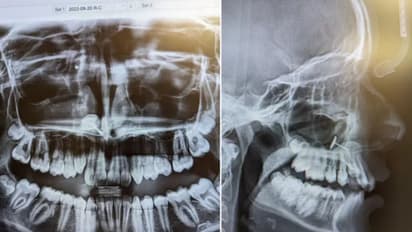

ದಿನನಿತ್ಯದ ದಂತ ಪರೀಕ್ಷೆಗೆಂದು ತಾಯಿ ಮತ್ತು ಮಗಳು ದಂತವೈದ್ಯರ ಬಳಿಗೆ ಹೋದಾಗ ಎಲ್ಲರನ್ನೂ ಬೆಚ್ಚಿಬೀಳಿಸುವ ಸಂಗತಿಯೊಂದು ಹೊರಬಿದ್ದಿದೆ. 13 ವರ್ಷದ ಬಾಲಕಿ ತನ್ನ ತಾಯಿಯೊಂದಿಗೆ ಬ್ರೇಸ್‌ ಹಾಕಿಸಿಕೊಳ್ಳಲು ಹೋಗಿದ್ದಳು. ಪರೀಕ್ಷೆಯ ನಂತರ, ವೈದ್ಯರು ಅವಳ ಎಕ್ಸ್-ರೇ ತೋರಿಸಿದಾಗ ಎಲ್ಲರೂ ಶಾಕ್ ಆದರು. ಹೌದು, ಎಕ್ಸ್-ರೇನಲ್ಲಿ ಅವಳ ಮೂಗಿನ ಬಳಿಯ ಸೈನಸ್‌ನಲ್ಲಿ ಕಿವಿಯೋಲೆಯ ಸಣ್ಣ ತುಂಡೊಂದು ಸಿಲುಕಿಕೊಂಡಿರುವುದು ತಿಳಿದುಬಂದಿದೆ. ಆದರೆ ಅದು ಅಲ್ಲಿಗೆ ಹೇಗೆ ಹೋಯ್ತು, ಅಲ್ಲಿ ಸಿಲುಕಿಕೊಳ್ಳಲು ಕಾರಣವೇನು? ಎಂಬುದೇ ಇಂಟ್ರೆಸ್ಟಿಂಗ್ ಆಗಿದೆ. ಎಲ್ಲಕ್ಕಿಂತ ಹೆಚ್ಚಾಗಿ ಎಡಿಎಚ್‌ಡಿ ಸಮಸ್ಯೆ ಇರುವವರು ಇದನ್ನು ತಿಳಿದುಕೊಳ್ಳಲೇಬೇಕಾಗಿದೆ.

ಕಿವಿಯೋಲೆಯ ತುಂಡು ಅಲ್ಲಿಗೆ ಹೇಗೆ ತಲುಪಿತು ಎಂಬುದರ ಬಗ್ಗೆ ಎಲ್ಲರೂ ಆಶ್ಚರ್ಯಚಕಿತರಾಗಿದ್ದರು. ವರದಿಯ ಪ್ರಕಾರ ( ref.) ಅಮೆರಿಕದ ವಾಷಿಂಗ್ಟನ್ ಸ್ಟೇಟ್‌ನಲ್ಲಿ ಕೆಲವು ತಿಂಗಳ ಹಿಂದೆ ಬಾಲಕಿ ತನ್ನ ಮೂಗು ಚುಚ್ಚಿಕೊಳ್ಳಲು ತನ್ನ ತಾಯಿಯಿಂದ ಅನುಮತಿ ಕೇಳಿದ್ದಳು. ಆದರೆ ಆಕೆಯ ತಾಯಿ ನಿರಾಕರಿಸಿದ್ದಳು. ಬಾಲಕಿಗೆ ಎಡಿಎಚ್‌ಡಿ(ADHD)ಎಂಬ ಮಾನಸಿಕ ಸಮಸ್ಯೆ ಇತ್ತು. ಈ ಸಮಸ್ಯೆಯಿರುವವರು ಹಠಾತ್ ನಿರ್ಧಾರಗಳನ್ನು ತೆಗೆದುಕೊಳ್ಳುತ್ತಾರೆ ಮತ್ತು ತನ್ನ ಮೇಲೆ ಕಡಿಮೆ ನಿಯಂತ್ರಣ ಹೊಂದಿರುತ್ತಾರೆ. ಇದೇ ಸಮಸ್ಯೆಯಿಂದಾಗಿ ಆಕೆ ಕಿವಿ ಚುಚ್ಚುವ ಕಿವಿಯೋಲೆ ತೆಗೆದುಕೊಂಡು ತನ್ನ ಮೂಗನ್ನು ತಾನೇ ಚುಚ್ಚಿಕೊಳ್ಳಲು ಪ್ರಯತ್ನಿಸಿದಳು. ಮೂಗಿನ ಒಳಭಾಗವನ್ನು ಚುಚ್ಚಲು ಪ್ರಯತ್ನಿಸುವಾಗ, ಅವಳು ಬಹುಶಃ ಸೀನಿರಬಹುದು ಅಥವಾ ಆಳವಾದ ಉಸಿರನ್ನು ತೆಗೆದುಕೊಂಡಿರಬಹುದು. ಈ ಪ್ರಕ್ರಿಯೆಯಲ್ಲಿ ಕಿವಿಯೋಲೆಯ ತುಂಡು ಒಳಗೆ ಎಳೆದುಕೊಂಡು ಅವಳ ಸೈನಸ್‌ಗಳಲ್ಲಿ ಸಿಲುಕಿಕೊಂಡಿತು. ಅವಳು ಭಯಭೀತಳಾಗಿ ಮುಜುಗರಕ್ಕೊಳಗಾಗಿದ್ದಳು. ಅದಕ್ಕಾಗಿಯೇ ತನ್ನ ತಾಯಿಗೆ ಏನನ್ನೂ ಹೇಳಲಿಲ್ಲ. ಅವಳಿಗೆ ಯಾವುದೇ ನೋವು ಅನಿಸದ ಕಾರಣ ಲೋಹವನ್ನು ಯಾರಾದರೂ ನುಂಗಿರಬಹುದು ಎಂದು ಭಾವಿಸಿದಳು.

ತಿಂಗಳುಗಟ್ಟಲೆ ಎಲ್ಲವೂ ಸಾಮಾನ್ಯವಾಗಿತ್ತು. ಆದರೆ ದಂತ ವೈದ್ಯರು ಎಕ್ಸ್-ರೇ ಮಾಡಿದಾಗ ಸಂಪೂರ್ಣ ಸತ್ಯ ಹೊರಬಂದಿದೆ. ವೈದ್ಯರು ಉದ್ದವಾದ ವೈದ್ಯಕೀಯ ಚಿಮಟ ಬಳಸಿ ಅದನ್ನು ಹೊರತೆಗೆದರು. ಸಂತಸದ ಸಂಗತಿಯೆಂದರೆ ಈ ಸಮಯದಲ್ಲಿ ಹುಡುಗಿಗೆ ಯಾವುದೇ ನೋವು ಅಥವಾ ಅಸ್ವಸ್ಥತೆ ಕಾಣಿಸಲಿಲ್ಲ. ಈ ಮೊದಲೇ ಹೇಳಿದ ಹಾಗೆ ಎಡಿಎಚ್‌ಡಿಯಿಂದ ಸಮಸ್ಯೆಯಿಂದ ಬಳಲುತ್ತಿರುವವರಿಗೆ ಗಮನ ಕೇಂದ್ರೀಕರಿಸಲು, ಸದ್ದಿಲ್ಲದೆ ಕುಳಿತುಕೊಳ್ಳಲು ಮತ್ತು ಚಿಂತನಶೀಲವಾಗಿ ಕೆಲಸ ಮಾಡಲು ಕಷ್ಟವಾಗುತ್ತದೆ. ತಾಯಿಯ ನಿರಾಕರಣೆಯ ಹೊರತಾಗಿಯೂ ಅವಳು ಲೋಹದ ವಸ್ತುವನ್ನು ತೆಗೆದುಕೊಂಡು ಮೂಗಿನಲ್ಲಿ ಹಾಕಿಕೊಳ್ಳಲು ಇದೇ ಕಾರಣ.